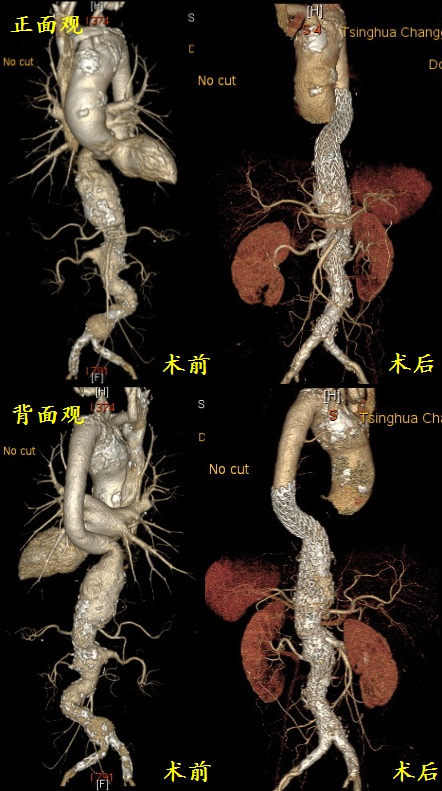

患者术前主动脉CTA

手术前后患者动脉形态比较